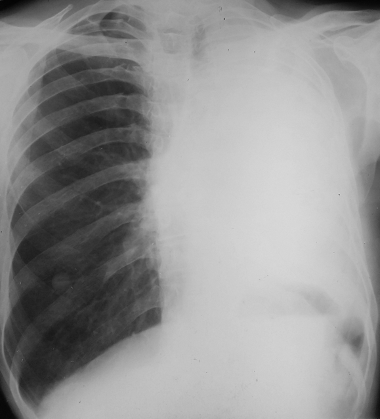

Rx toracică, incidență P-A

DESCRIERE:

la niv. întregului hemitorace stg → opacitate extinsă, nesistematizată, de intensitate mare, omogenă

caracter retractil → tracționează traheea și mediastinul de partea afectată

fără bronhogramă aerică

duce la micșorarea spațiilor intercostale

la niv. hemitoracelui controlateral → hipertransparență compensatorie (emfizem)

DX: atelectazie prin NBP central endobronșic (pe bronhia principală stg)

DD: pleurezie masivă → caracter expansiv